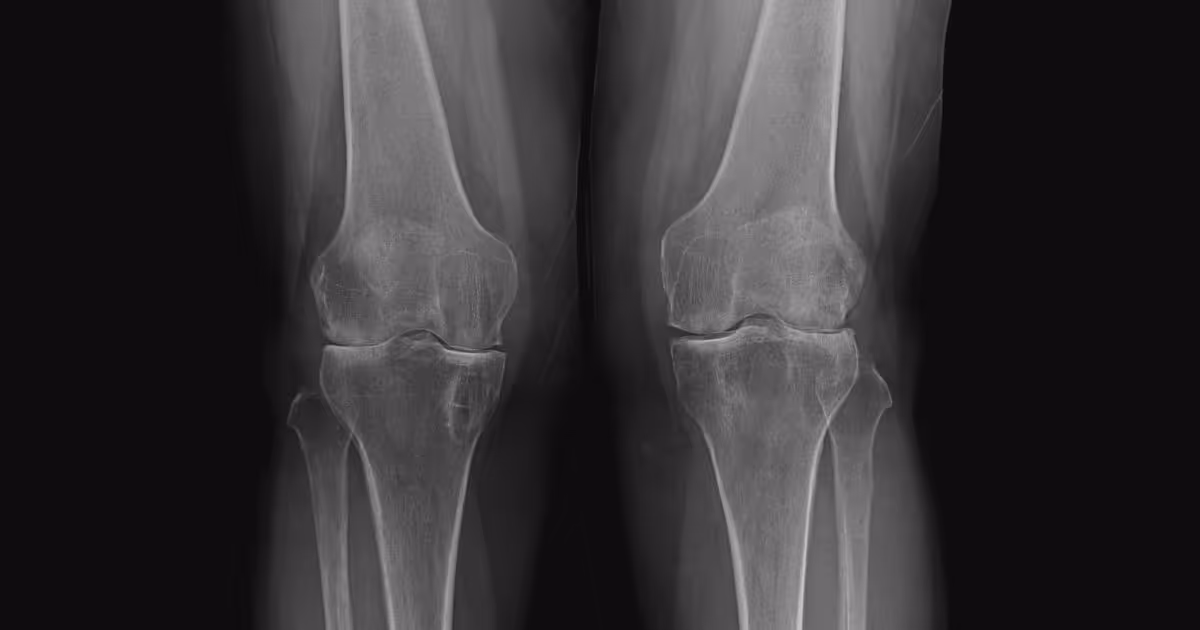

• X-rays to detect bone fractures and degenerative joint disease.